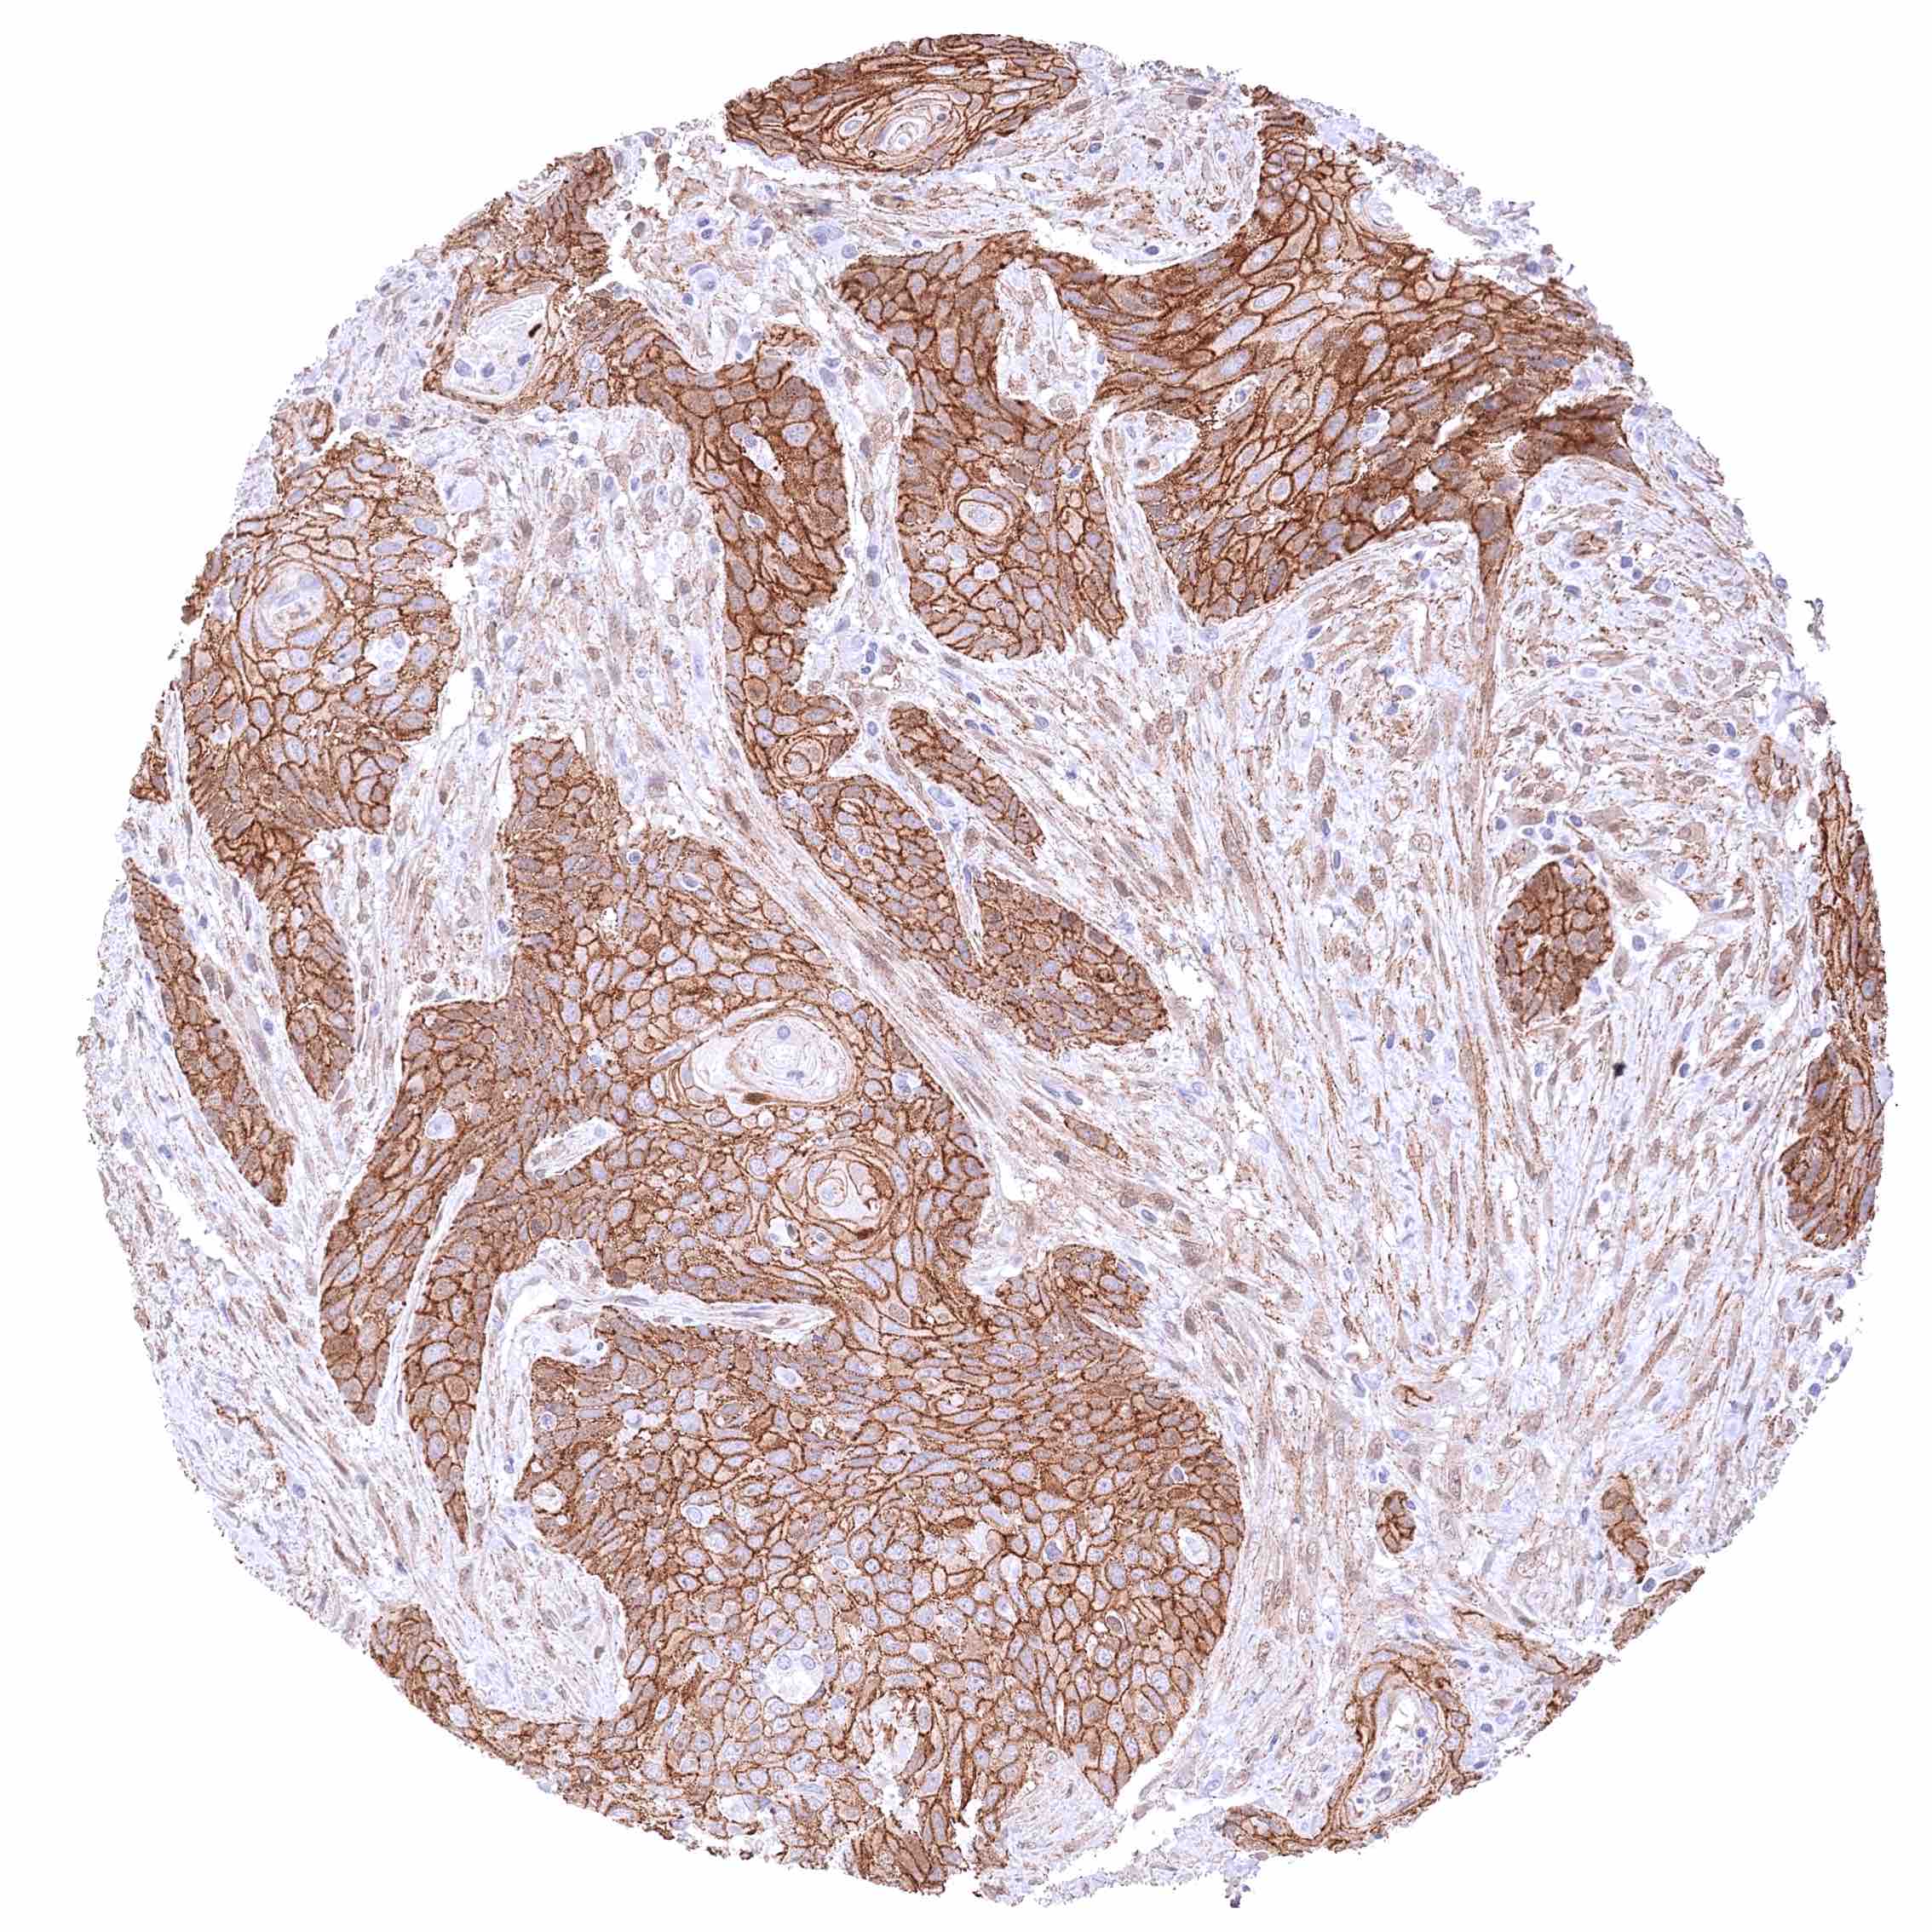

Uterus, cervix – Squamous cell carcinoma with strong membranous β-Catenin positivity of tumor cells.